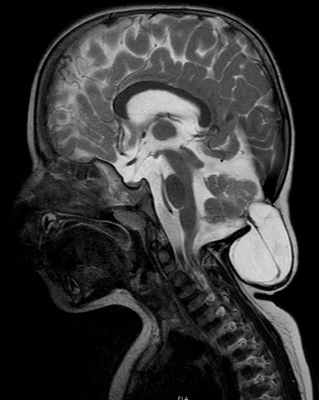

МРТ головного мозга при ААК III типа (энцефаломенингоцеле)